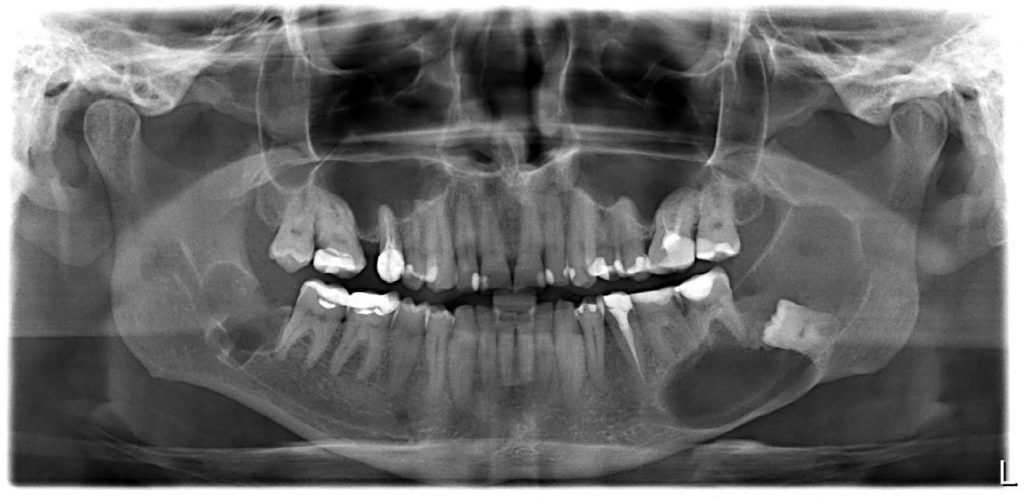

Sterowana regeneracja kostna z wykorzystaniem wiórów kości gąbczastej pobranej z piszczeli w dużych ubytkach kostnych szczęki i żuchwy powstałych w wyniku wyłuszczenia zmian o charakterze torbieli

TITLE: Guided Bone Regeneration using tibia bone graft, for the reconstruction of giant intrabone defects in mandible and maxilla, after removal of odontogenic cysts

Materiał i metoda. Retrospektywną analizą objęto 24 pacjentów, operowanych w latach 2014-2017, u których stwierdzono duży ubytek kostny. Sterowaną regenerację kostną przeprowadzono z wykorzystaniem autogennych wiórów kości gąbczastej pobranej z kości piszczelowej.

Wyniki. U wszystkich pacjentów stwierdzono prawidłową przebudowę kostną. Do powikłań zaliczono rozejście się brzegów rany, obecność parestezji oraz ból kończyny operowanej.